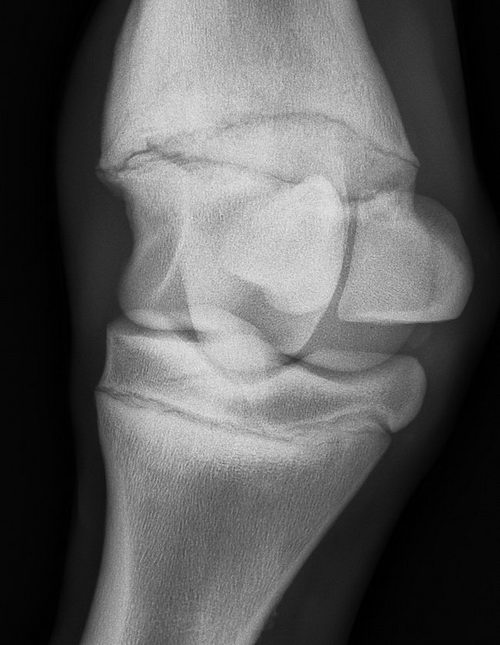

I cant seem to get an answer whether my colt has an OCD lesion or not. It is obvious that he has Physitis. Any ideas? Denise

The problem Denise is radiographs cannot positively answer your question. It can provide evidence that there is not a lesion but OCD can exist even without radiographic evidence. I see no evidence of OCD in the above radiograph but this judgement should be made from a minimum of 4 views and with the radiographic images directly in hand. There is a odd radio-opaque body just below the sesamoid on the left...hmmm it could be soft tissue consistency, perhaps a spot caused by the ergot? I would have to see the horse and other views to know for sure as the ergot is quite variable. Ann the physitis is best characterised by the lipping on the margin of the growth plate but I judge this for a 6 month old as mild and questionable significance. I suggest for a definitive answer you have the radiographs forwarded to a veterinary radiologist for evaluation however sometimes OCD exists before there is radiographic evidence. DrO